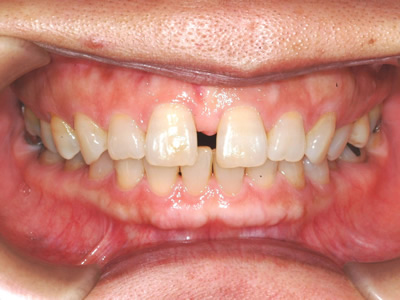

上顎の劣成長 (成長不足) による反対咬合で、上顎は拡大装置と上顎前方牽引装置を併用し前方方向への成長を促して前歯の咬み合わせを改善した後に、上下顎の前歯をマルチブラケット装置で並べました。治療の期間は2年でした。

初診時